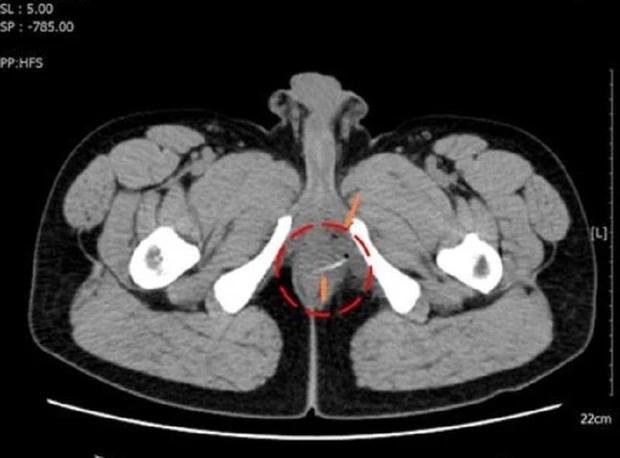

Bệnh nhân được chụp CT-Scan truy tìm nguyên nhân gây đau bất thường ở vùng hậu môn

Trên hình ảnh kiểm tra, bác sĩ phát hiện vùng đại tràng của bệnh nhân có dị vật cản quang hình que kèm bóng khí. Bệnh nhân đã được chỉ định nhập viện phẫu thuật.

Hình ảnh kiểm tra phát hiện chiếc xương cá cản quang ở vị trí trực tràng của bệnh nhân

Trong quá trình mổ, ê kíp phát hiện chiếc xương cá dài khoảng 3cm nằm ở vùng trực tràng, đâm thủng thành ruột và tạo áp xe nhưng may mắn chưa gặp biến chứng nguy hiểm.